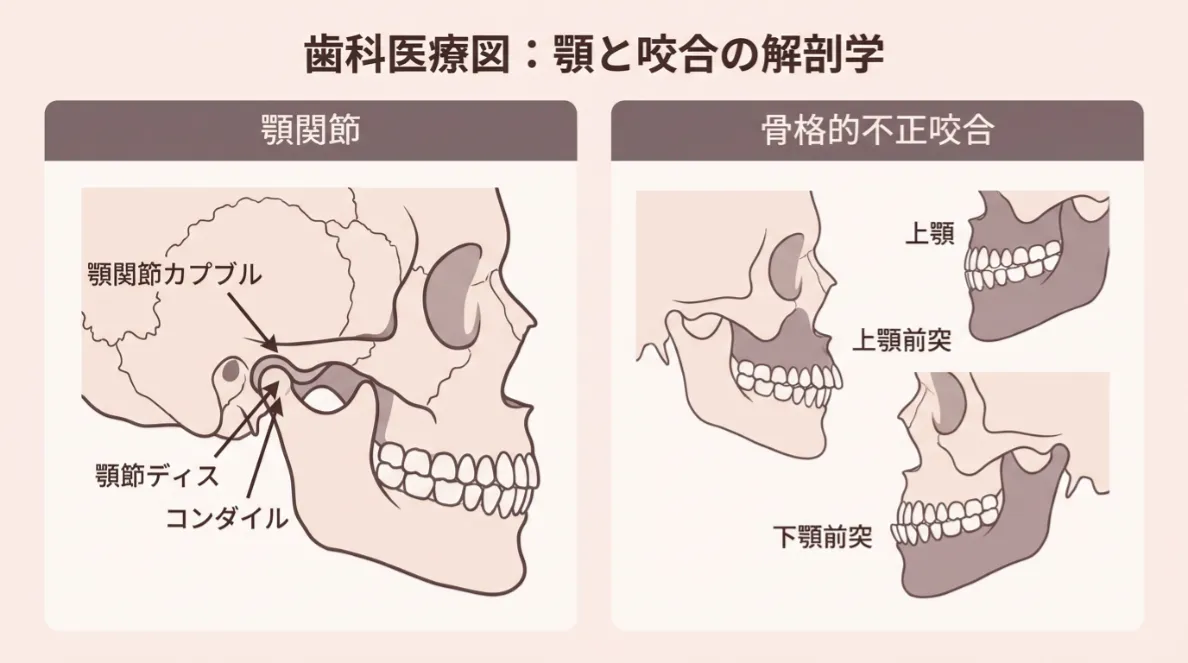

矯正治療は「どんな装置を使うか」よりも、診断の正確さが結果を大きく左右します。当院では、矯正診療を担当する歯科医師が、骨格やあごの動き、かみ合わせ、これまでの治療歴などをトータルで診断します。

あごや骨格に大きなズレがある方

骨格的なズレや顎関節症の程度が大きい場合、外科的矯正・ワイヤー矯正・アンカースクリューなどを組み合わせることがあります。

当院では一般歯科治療から矯正までを一貫して行えるため、治療を分けて通う必要はありません。CT撮影による立体的な診断を行い、長く安定するかみ合わせを設計します。